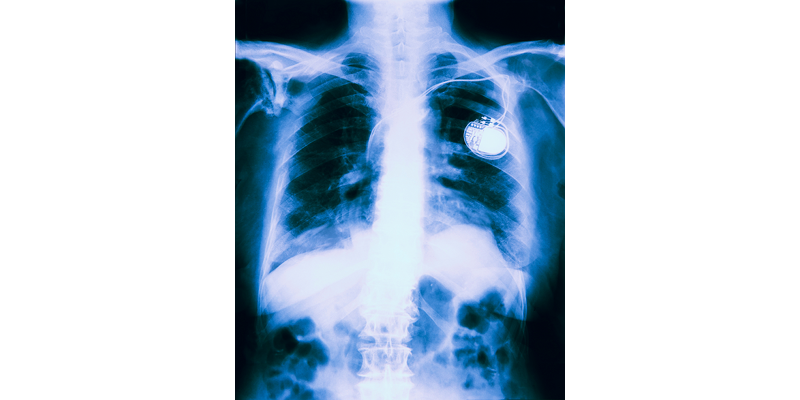

Een sideraal is in staat 600 volt en 100 watt aan energie te genereren, die het vervolgens kan inzetten om een prooi te verdoven of zichzelf te verdedigen. Onderzoekers willen dit vermogen van de sideraal gebruiken om systeem te ontwikkelen dat kleine medische implantaten zoals pacemakers van energie kan voorzien. Het systeem moet in het menselijk lichaam energie uit bijvoorbeeld de spieren of metabolische energie winnen en opslaan, zodat deze vervolgens gecontroleerd kan worden afgegeven aan het implantaat.